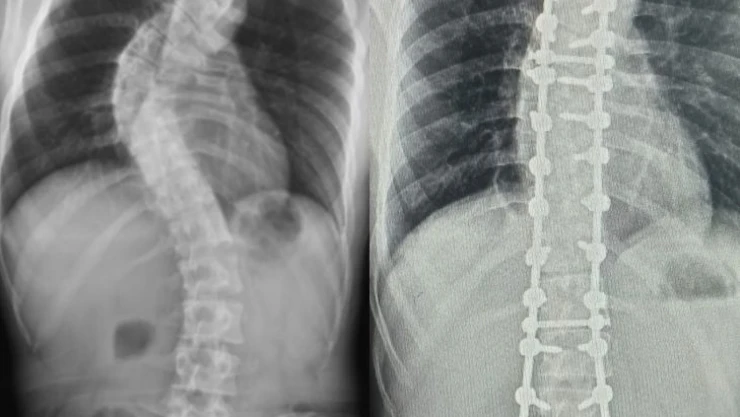

Yapılan muayene ve incelemeler sonucu hastada 73 derece skolyoz (omurga eğriliği) ve kifoz (kamburluk) tespit edilerek Ahmet Akan’a ameliyat önerildi. Samsun Üniversitesi Tıp Fakültesi Ortopedi ve Travmatoloji Anabilim Dalı Öğretim Üyelerinden Dr. Öğr. Üyesi Ömer Bozduman, deneyimli ameliyat ve anestezi ekibi eşliğinde görev yaptığı Samsun Eğitim ve Araştırma Hastanesi’nde 7 saat süren başarılı bir skolyoz ameliyatı gerçekleştirdi.

Hasta ile ilgili bilgi veren Dr. Öğretim Üyesi Ömer Bozduman, “Hastamız artan sırt ağrıları ve omurga eğriliğinin ilerlemesi şikâyetiyle kliniğimize başvurdu. İnceleme ve değerlendirmelerimiz sonucu ameliyat kararı verdik. 7 saat süren skolyoz ameliyatını takiben 12 saat sonra hastamız kaldırılıp yürütüldü. Ameliyat sonrası nörolojik olarak hiçbir sorunu yok. Eğriliği tamamen düzeldi, boyu uzadı. Şu an kendisi yürüyüp gezebiliyor. Hastayı 5 gün sonra taburcu edip evine gönderiyoruz. Her ameliyatta olduğu gibi skolyoz ameliyatlarında da ekip çalışması çok önemlidir. Uzun süren bu ameliyatı, hastanemizin özverili ameliyat ve servis hemşireleri ve deneyimli anestezi ekibi ile gerçekleştirdik” dedi.